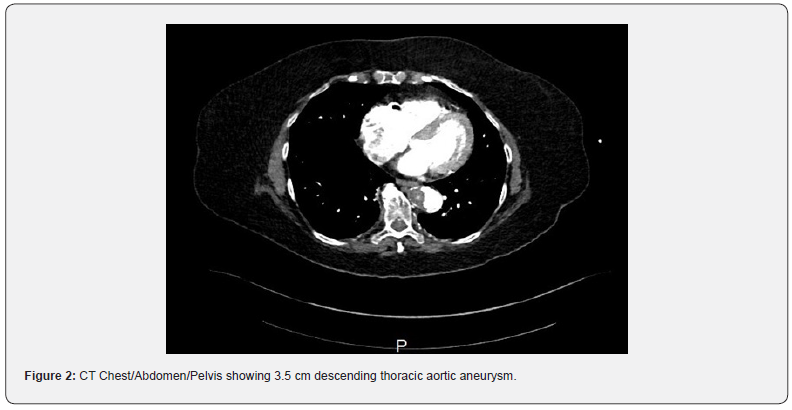

Case Presentation: A patient with multiple comorbidities including coronary artery disease and peripheral artery disease (Rutherford 4 symptoms bilaterally) presented to the emergency room with chest pain and dyspnea on exertion. The patient was found to have a 3.5 cm descending thoracic aortic aneurysm, multiple penetrating aortic ulcers (PAU’s) within the descending thoracic aorta which was felt to be the cause of her chest pain along with heavily calcified occlusive aorto-iliac disease. The patient was deemed high surgical risk for open repair and the patient’s severe calcific distal aortic stenosis and bilateral severe ostial iliac stenosis was deemed a barrier for endovascular repair. Therefore, the patient was successfully treated with kissing balloon lithoplasty for lesion preparation of the heavy calcification and placement of an endovascular stent graft (EVAR) in the distal aorta, which ensured a safe conduit for thoracic endovascular aortic repair (TEVAR) procedure.

73-year-old female with past medical history of non-insulin dependent diabetes mellitus, hypertension, hyperlipidemia, coronary artery disease (stent to the distal and mid right coronary artery [RCA]), and peripheral artery disease (Rutherford 4 symptoms bilaterally) presented to the emergency department for sudden onset chest pain and dyspnea on exertion. Patient had multiple previous admissions with similar complaints for chest pain and had multiple biochemical assays and imaging studies including coronary angiography to evaluate for coronary artery disease, which were negative. During this admission, the patient underwent CT angiography which demonstrated a 3.5 cm descending thoracic aortic aneurysm, multiple PAU’s within the descending thoracic aorta, a severely calcified distal aortic stenosis and bilateral severe ostial iliac stenosis (Figures 1-3). Given recurrent admissions and negative cardiac work up, the thoracic penetrating aortic ulcer was thought to be the etiology of her chest pain. There was concern regarding the treatment of the thoracic penetrating ulcer as the patient was ultimately deemed high-risk for surgical repair and there was no clear conduit to get to the thoracic aorta by an endovascular approach due to the severe distal aorto-iliac occlusive disease. After discussions between vascular surgery and interventional cardiology, a decision was made to proceed initially to treat the severe distal aorto-iliac stenosis with a bifurcated stent graft to ensure a clear endovascular passage to ultimately treat the thoracic aortic disease. Calcium, plaque modification and possible stenting was deemed a necessary and warranted strategy for lesion preparation to help facilitate the large TEVAR delivery system. Lack of proper lesion preparation of heavy calcificed lesions can lead to complications such as dissection, perforation, inability to advance the device, and ultimately failure of the procedure. Intravascular balloon lithoplasty has shown favorable results in recent clinical experience in the realm of structural heart disease in order to complete transcatheter aortic valve replacement (TAVR) procedures therefore this method of lesion preparation was chosen for this case [7,8]. Intravascular lithoplasty functions by incorporating lithoplasty emitters within an angioplasty balloon, such that sonic pressure waves drive through surrounding tissue selectively fracturing vascular calcium within the vessel wall, thus purportedly altering vessel compliance and permitting vessel dilation at relatively low pressures. Other methods to prepare the lesions such as balloon angioplasty or atherectomy were considered but was believed that it was inadequate and may leave residual stenosis and unsatisfactory result within the artery.